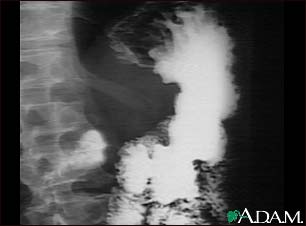

Stomach cancer, X-ray

An upper GI series in a patient with cancer of the stomach (gastric carcinoma).